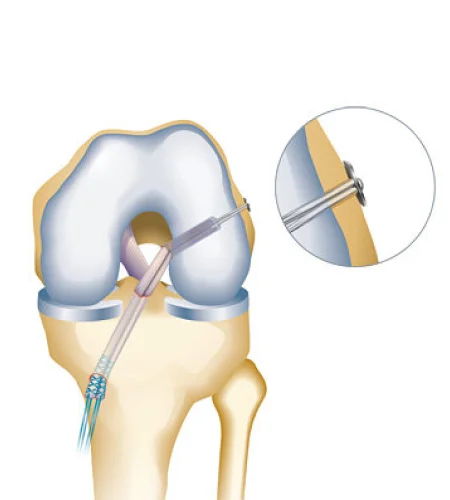

ACL Reconstruction

Surgical repair of the anterior cruciate ligament to restore knee stability and prevent further damage.